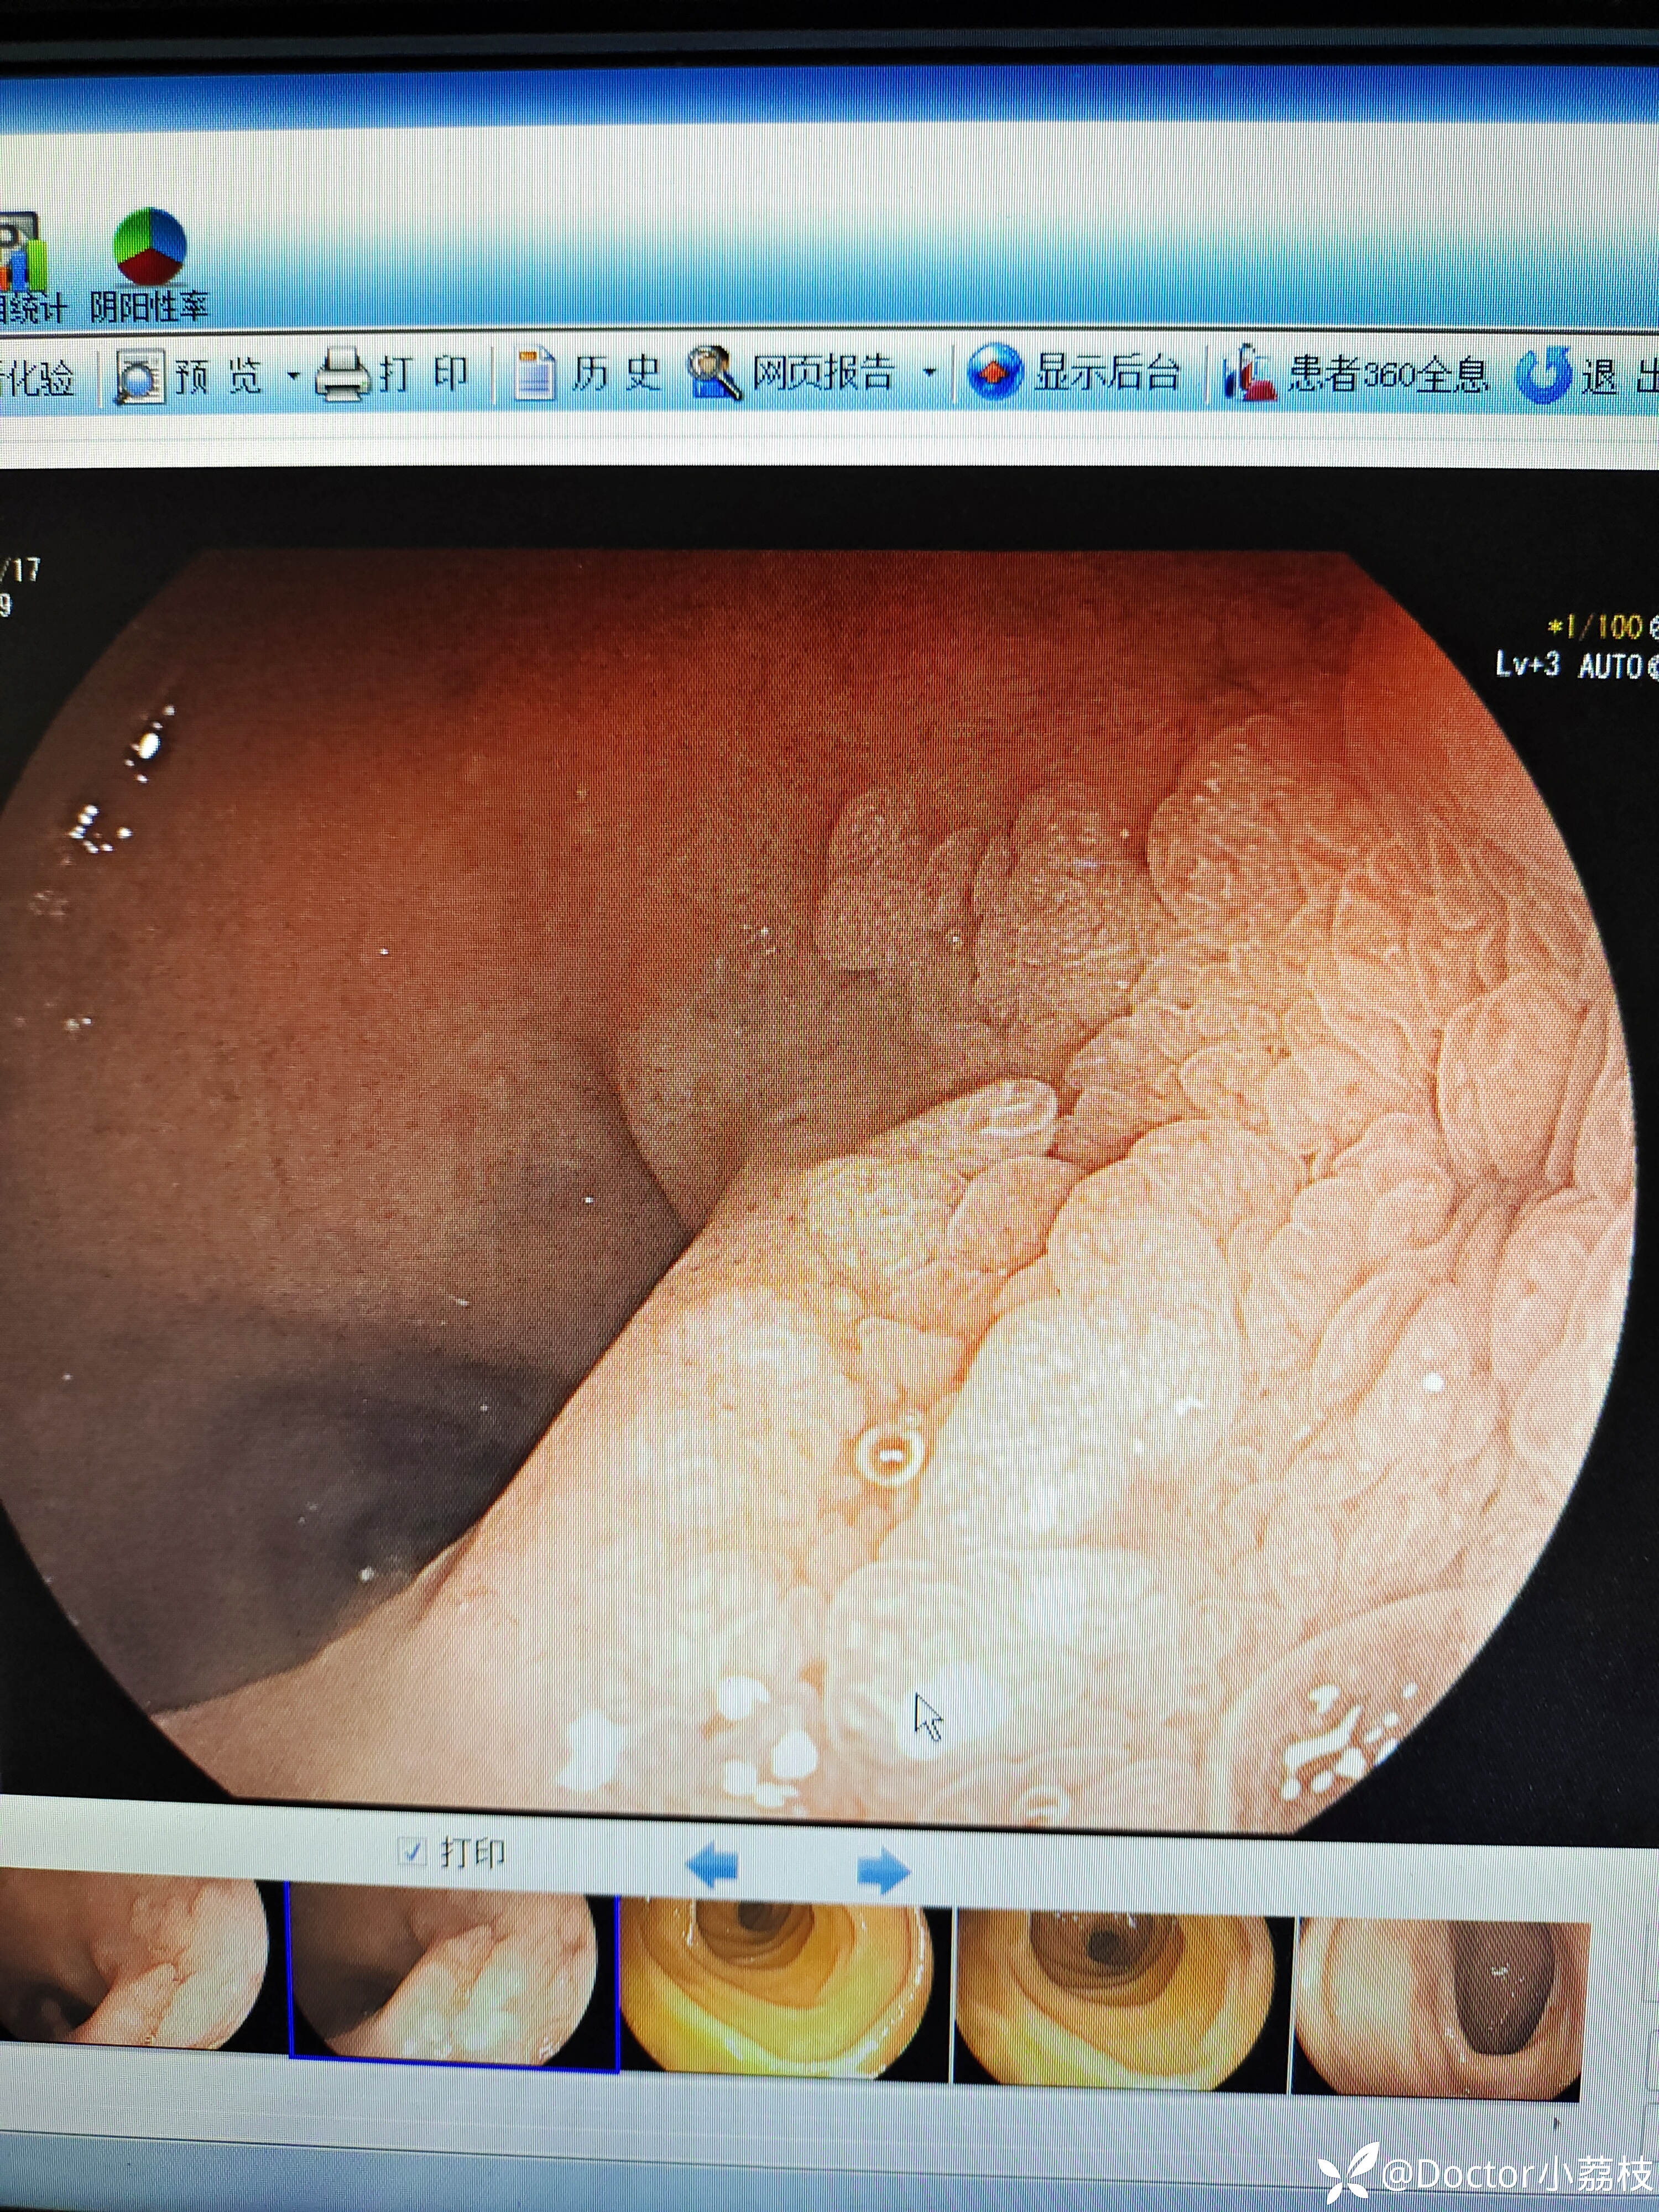

今天做胃镜发现的,患者因胆囊结石于肝胆外科就诊,拟行腹腔镜下胆囊切除,自诉两日前黑便一次,此后大便转黄。今日行胃镜见12指肠后壁病变。我是胃镜初学,想请教各位前辈,这个病变考虑什么